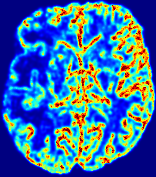

4.3.2 Diffusion Imaging via Advection-Diffusion

Slice #1Slice #2Slice #3Slice #4Slice #5Slice #6Dgtsuperscript𝐷gtD^{\text{gt}}Refer to captionRefer to captionRefer to captionRefer to captionRefer to captionRefer to captionDestsuperscript𝐷estD^{\text{est}}Refer to captionRefer to captionRefer to captionRefer to captionRefer to captionRefer to captionRefer to caption0.300.300.300.240.240.240.180.180.180.120.120.120.060.060.060.000.000.00(mm2/s)𝑚superscript𝑚2𝑠(mm^{2}/s)𝐕est𝟐subscriptnormsuperscript𝐕est2\|\bf{V}^{\text{est}}\|_{2}Refer to captionRefer to captionRefer to captionRefer to captionRefer to captionRefer to captionRefer to caption0.00300.00300.00300.00240.00240.00240.00180.00180.00180.00120.00120.00120.00060.00060.00060.00000.00000.0000(mm/s)𝑚𝑚𝑠(mm/s)

Figure 15: PIANO identifiability testing: diffusion imaging via advection-diffusion. Top row shows Dgtsuperscript𝐷gtD^{\text{gt}} used for simulating ground truth pure diffusion. Rows below show the estimated Destsuperscript𝐷estD^{\text{est}} and 𝐕est2subscriptnormsuperscript𝐕est2\|{\bf{V}}^{\text{est}}\|_{2} on corresponding slices. Note that the plotted value scale for 𝐕est2subscriptnormsuperscript𝐕est2\|{\bf{V}}^{\text{est}}\|_{2} is 0.01 of that for Dgtsuperscript𝐷gtD^{\text{gt}} and Destsuperscript𝐷estD^{\text{est}}.

Similarly, we test the behavior of PIANO when estimating both advection and diffusion from a pure diffusion-driven process. The goal is to determine if PIANO is able to recognize that there is only diffusion governing the given concentration time-series. We use the same ‘Diffusion Imaging’ data simulation of Sec. 4.2.1 as the concentration dataset, PIANO estimates both velocity 𝐕estsuperscript𝐕est{\bf{V}}^{\text{est}} and diffusivity Destsuperscript𝐷estD^{\text{est}}. Estimation results in Fig. 15 confirm PIANO’s identifiability again: the estimated 𝐕est2subscriptnormsuperscript𝐕est2\|{\bf{V}}^{\text{est}}\|_{2} is almost invisible compared to Destsuperscript𝐷estD^{\text{est}}, even plotted with a 1%percent11\% value range compared to that for Destsuperscript𝐷estD^{\text{est}}. On the other hand, Destsuperscript𝐷estD^{\text{est}} achieves comparable estimation performance as ‘Diffusion Imaging via Diffusion’ in which PIANO predicts Destsuperscript𝐷estD^{\text{est}} alone (shown in Fig. 13).